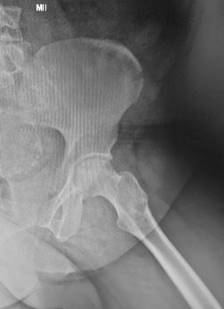

Figura 1: A) Radiografía anteroposterior de caderas con área de necrosis de cabeza femoral. B) Radiografía lateral de caderas con área de necrosis de cabeza femoral.

Todos los pacientes habían recibido corticosteroides como parte de su régimen de tratamiento para COVID-19 con dosis promedio de 480 mg, en un rango de 400 a 1,200 mg de hidrocortisona (o su equivalente -se adjunta Tabla de conversión-) (Tabla 1). Estos pacientes mostraron síntomas clásicos de NAVCF caracterizados por un rápido deterioro funcional con sintomatología clínica de dolor, limitación a la carga y movilización. Asimismo, presentaron los cambios correspondientes en las imágenes de radiografías y resonancia magnética nuclear (RMN); los estadios de necrosis fueron clasificados según Ficat8 (Figuras 1 y 2). Se incluyeron estadios I a III de la clasificación dada la juventud de la serie y que no tenían artrosis con disminución del espacio articular.